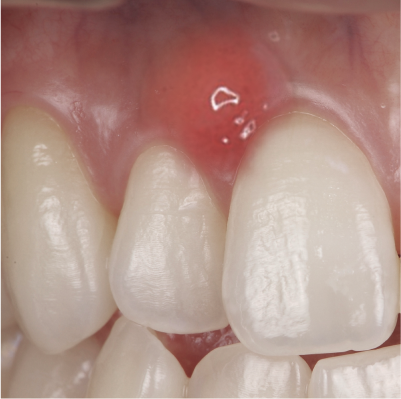

• 妊娠性歯肉炎の症例写真

妊娠性歯肉炎

歯肉の腫れや赤み、出血する方は可能性が高いです。歯周病へと悪化すると早産リスクを高めるため、早めに医師に相談しましょう。